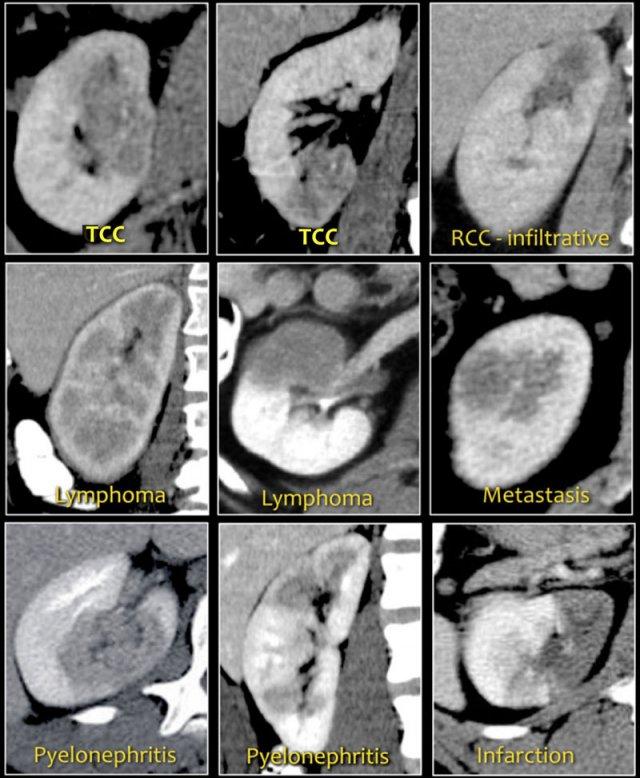

Tổn thương dạng hạt đậu

Các đặc điểm hình ảnh của tổn thương dạng hạt đậu thường không đặc hiệu.

Lưu ý sự tương đồng về hình ảnh của các tổn thương trong hình.

Chẩn đoán phân biệt thường có thể được gợi ý bằng cách tích hợp dữ liệu lâm sàng và hình ảnh.

- Tổn thương thâm nhiễm trung tâm lấp đầy bể thận ở bệnh nhân lớn tuổi nhiều khả năng là ung thư biểu mô tế bào chuyển tiếp (TCC), còn gọi là ung thư biểu mô tế bào niệu mạc (UCC).

- Khối thâm nhiễm ở bệnh nhân trẻ có đặc điểm hồng cầu hình liềm nhiều khả năng là ung thư biểu mô tủy thận.

- Tổn thương đa ổ và hai bên hoặc thâm nhiễm thận lan tỏa kết hợp với hạch bạch huyết to và tổn thương các cơ quan khác gợi ý u lympho.

- Tổn thương thận đa ổ và hai bên trong bệnh ác tính đã biết gợi ý di căn, mặc dù trong trường hợp một khối thâm nhiễm đơn độc, cần xem xét ung thư biểu mô tế bào thận thể thâm nhiễm.

- Ở bệnh nhân có đau và dấu hiệu nhiễm trùng, chẩn đoán là viêm thận bể thận.

- Tổn thương hình nêm gợi ý nhồi máu thận.